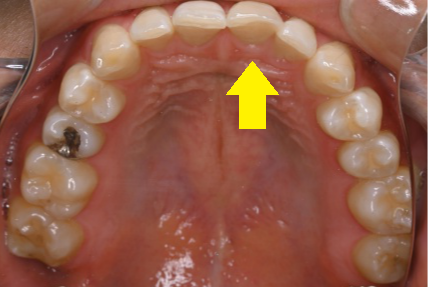

↑むし歯で弱く(もろく)なっていた部分が、食事中に欠けてしまったケース